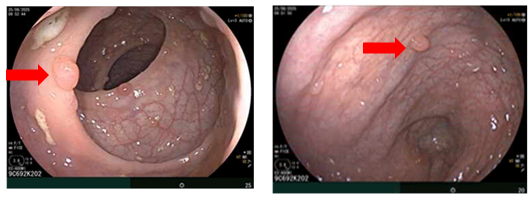

- Nội soi dạ dày: Thân phình vị, thân vị có đám niêm mạc co kéo, hội tụ, lõm ở trung tâm kích thước~ 3.0cm, bề mặt niêm mạc biến đổi

Hình 2

. Hình ảnh các polyp ở dạ dày (mũi tên đỏ). Niêm mạc dạ dày co kéo, lõm ở trung tâm (mũi tên xanh)